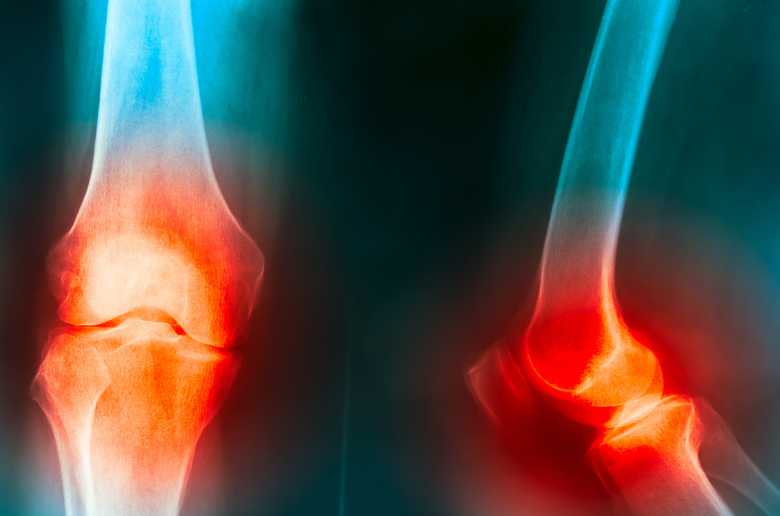

退化性關節炎是一種常見的關節疾病,尤其在中老年人群中更為普遍。這種疾病的特徵是關節軟骨逐漸退化,導致骨骼摩擦,從而引起疼痛、僵硬和活動受限。雖然退化性關節炎無法完全治愈,但通過早期識別症狀和採取預防措施,可以顯著減緩其進展,改善生活質量。在這篇文章中,我們將詳細探討退化性關節炎的早期徵兆,以及如何通過簡單的生活方式改變來防止這種疾病的發展。

關節疼痛的原因在於關節軟骨的磨損,導致骨骼之間直接摩擦,引起炎症和疼痛。隨著時間的推移,這種疼痛可能會影響到日常生活,甚至使簡單的活動變得困難。

關節腫脹的原因是由於軟骨的損傷和關節內的炎症反應。當軟骨磨損後,骨骼之間的摩擦增加,導致關節內部的炎症,進而引起腫脹和疼痛。

最後,退化性關節炎的一個明顯徵兆是關節活動時發出的聲音,如咔咔聲或摩擦聲。這種聲音通常是在軟骨磨損後,骨骼之間直接接觸和摩擦時產生的。雖然關節聲音本身並不一定會引起疼痛,但它是關節退化的一個警示信號。

關節聲音的原因是由於軟骨的退化和損傷,導致骨骼之間的摩擦增加。這種聲音可能會隨著病情的進展變得更加明顯,是退化性關節炎的重要徵兆之一。